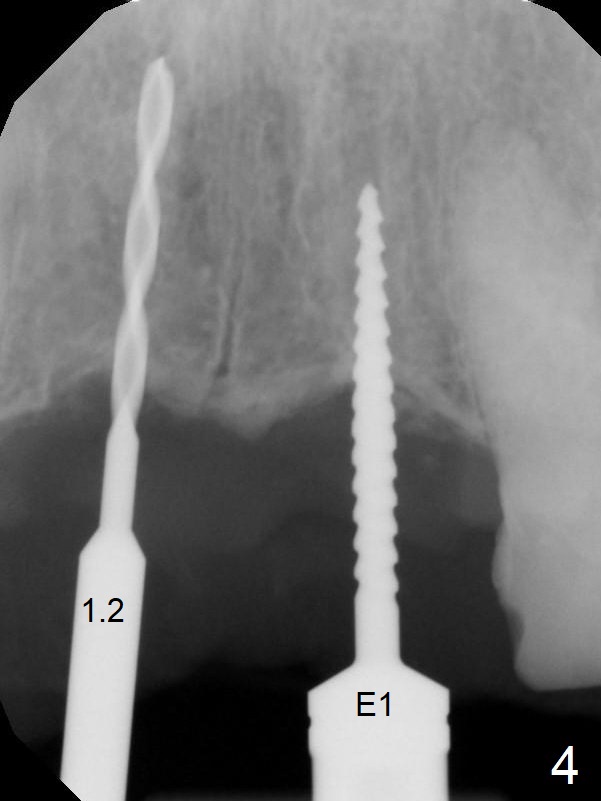

A 45-year-old Spanish woman requests implants to replace #7-10 FPD (Fig.1,2,7). After incision, osteotomy is initiated in the palatal aspect of the crest with 1.2 mm drill and DIO Bone Expanders (E1 (diameter 1.0/1.6 mm),E2 (1.3/2.3 mm), Fig.3,4). Following adjustment of the trajectory (to avoid invasion of the Incisive Canal (Fig.2 *) and use of E3 (1.7/3.1 mm), two of 3.5x11.5 mm HIOSSEN implants are placed with satisfactory stability (Fig.5). With Vanilla graft (Fig.5 *) placed over the palatally-exposed coronal threads, the flaps are approximated (Fig.6). The FPD is recemented temporarily (Fig.7).